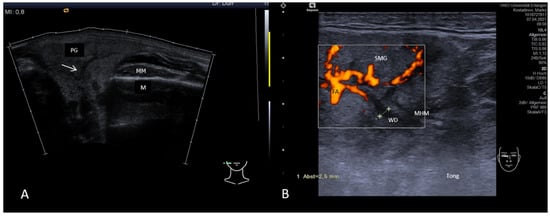

3.5. Ultrasound in Monitoring Gland Function at the Follow-up Examination in Inflammatory and Obstructive Salivary Gland Disease